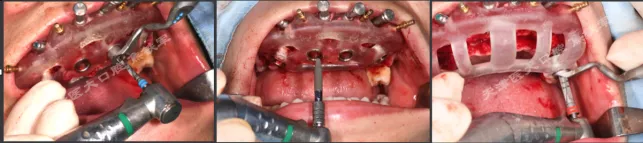

· 基部导板上缘做为截骨线,精确去骨,平整骨面。

· 全程植入导板就位于基部导板上,固位钉固定,引导种植体植入。

· 拔除部分牙齿,翻瓣,利用剩余牙齿支持组合导板,辅助基部导板就位固定,基部导板上缘做为去骨线,精确去骨。

· 全程导板就位,引导种植体植入,安装复合基台。

· 种植体植入位置偏腭侧,唇侧骨量过于丰满,上颌骨前突,去骨修整骨边缘。